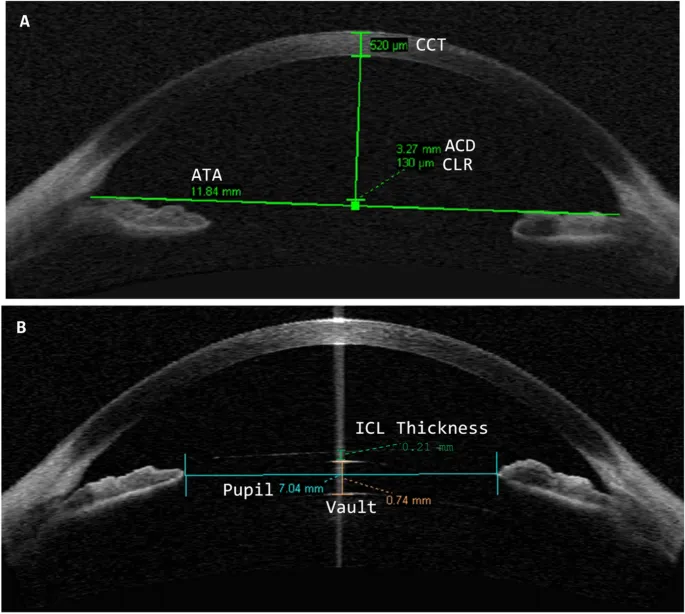

- Sizing is Key: Proper sizing ensures adequate vault for Posterior Chamber IOLs, preventing complications.

⭐ Accurate White-to-White (WTW) is crucial for sizing anterior chamber phakic IOLs; ACD is key for posterior chamber IOL vault.

- Cataract formation: Esp. PC IOLs if vault low.

⭐ PC Phakic IOLs touching the crystalline lens (low vault) are a significant risk for anterior subcapsular cataract.

- ICL sizing is crucial; incorrect sizing risks vault issues, cataract formation, or angle closure.